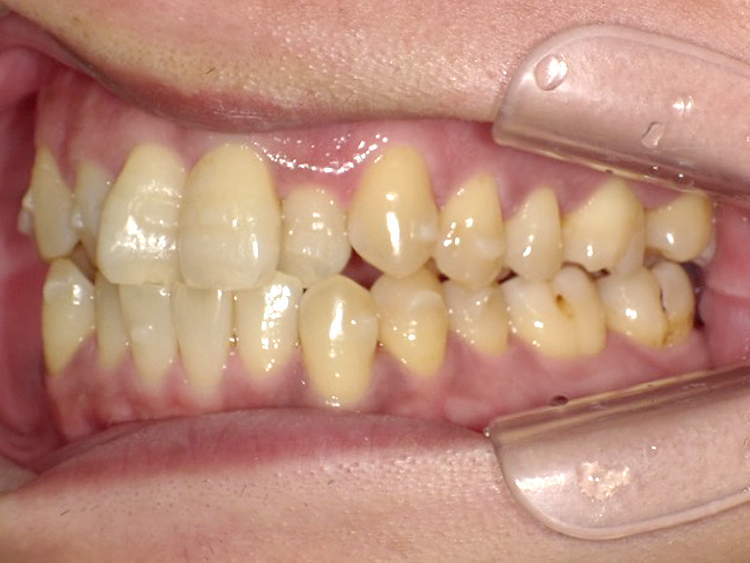

症例4

Before

After

| 主訴 | 上下前歯のがたつき |

|---|---|

| 年齢 | --- |

| 治療 期間 |

約9ヶ月 |

| 治療 内容 |

インビザラインiGoで上下顎の治療。 |

| 治療費 | ¥550,000(税込)/調整料含む |

| 治療のリスク | 矯正終了後は、リテーナーを指示通りに使用し、歯の後戻りを防ぐ必要があります。 |